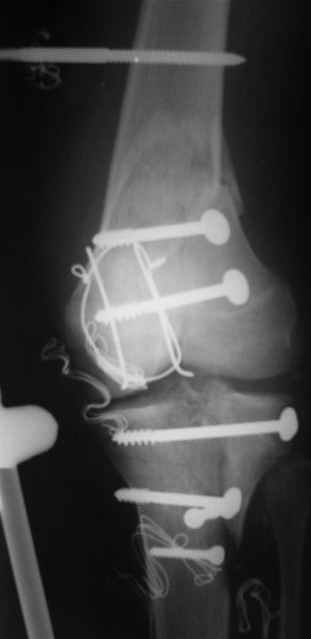

Re: открытый перелом мыщелков бедра, латерального

Alexander Chelnokov 14 Декабрь 2004, 18:23

ET> обработку и внешнюю фиксацию, картинки в приложении.

Спасибо за комментарии. Травма тяжелая с проблематичным прогнозом для функции коленного сустава( изначально травма разгибательного аппарата с последующим частичным некрозом собственной связки надколенника и о обнажением рефиксированного фрагмента бугристости большеберцовой кости, дефектом центрального отдела суставной поверхности большеберцовой кости и медиального отдела капсулы сустава).